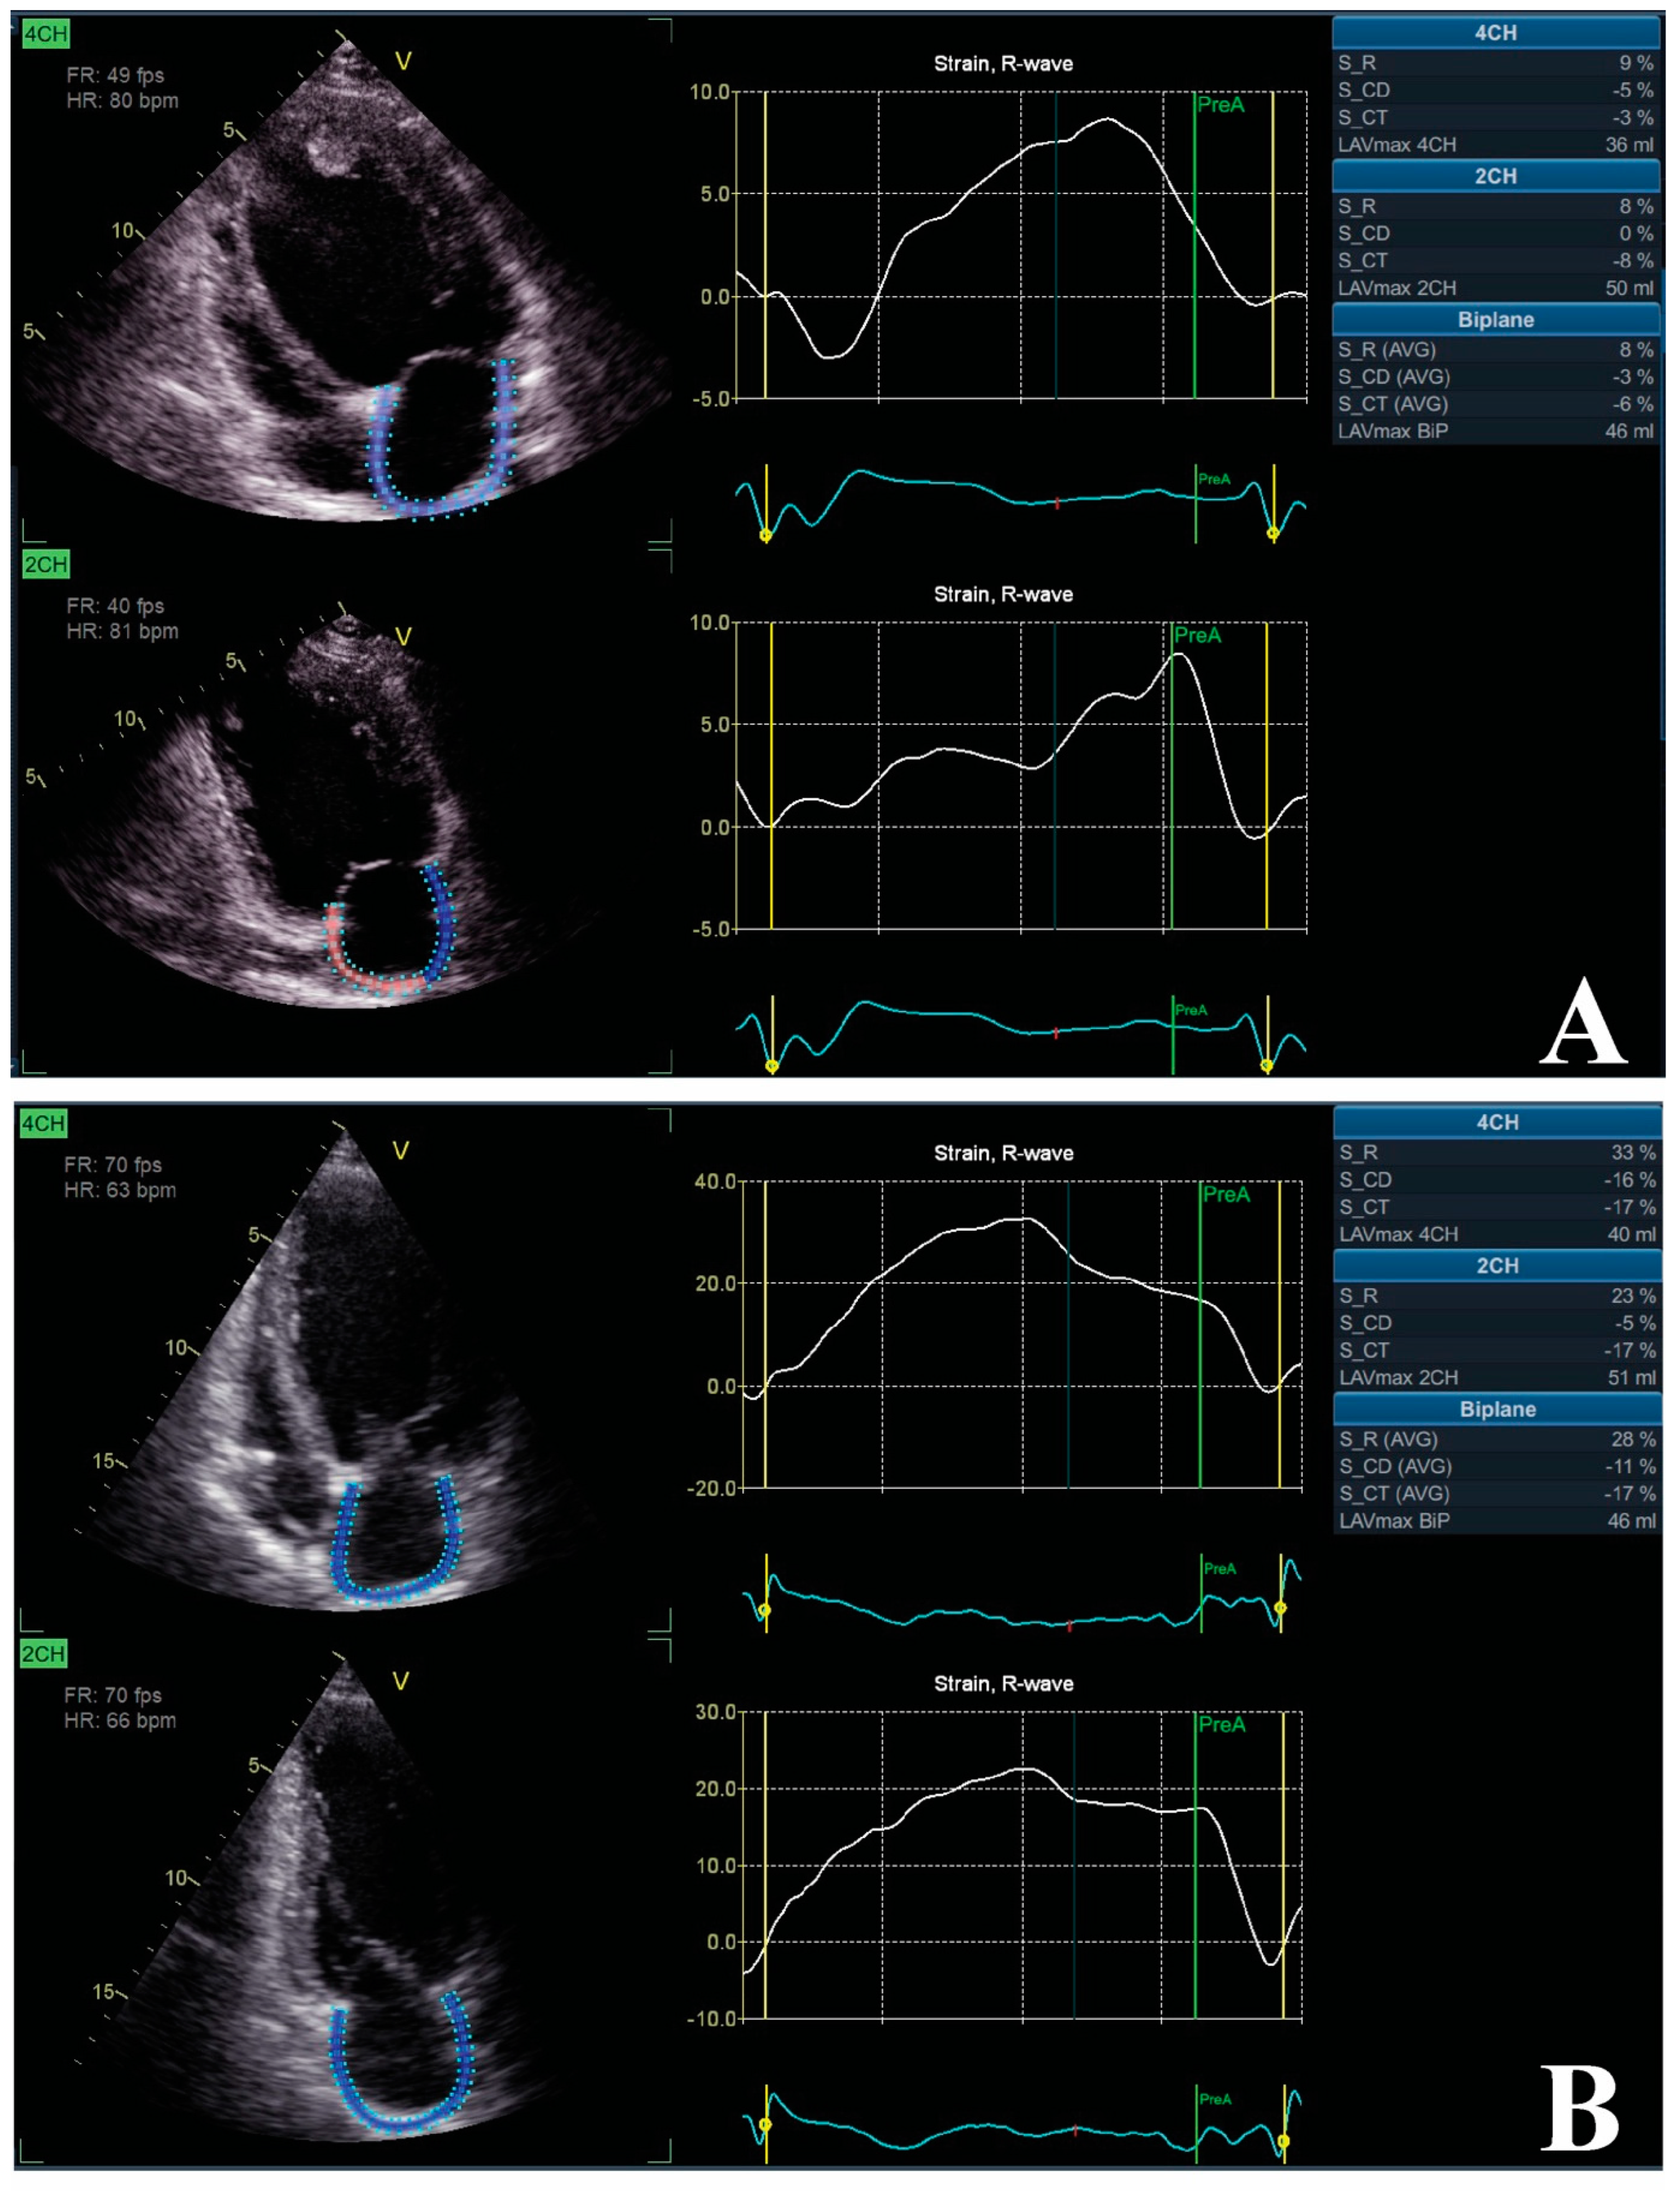

5.2. LA Phasic Function and Strain